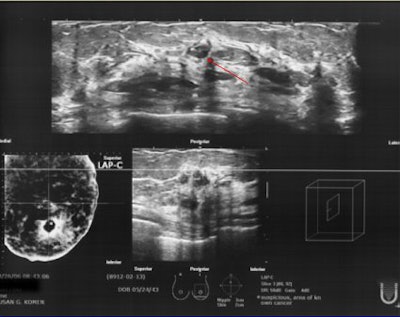

| 62-year-old patient underwent bilateral screening mammogram and was called back for additional imaging of a posterior left breast asymmetry and anterior left breast calcifications. On ABUS, the first diagnosed left breast cancer can be seen at 12 o'clock, 3 cm from the nipple, corresponding to site of subareolar calcifications seen mammographically (infiltrating ductal carcinoma). |